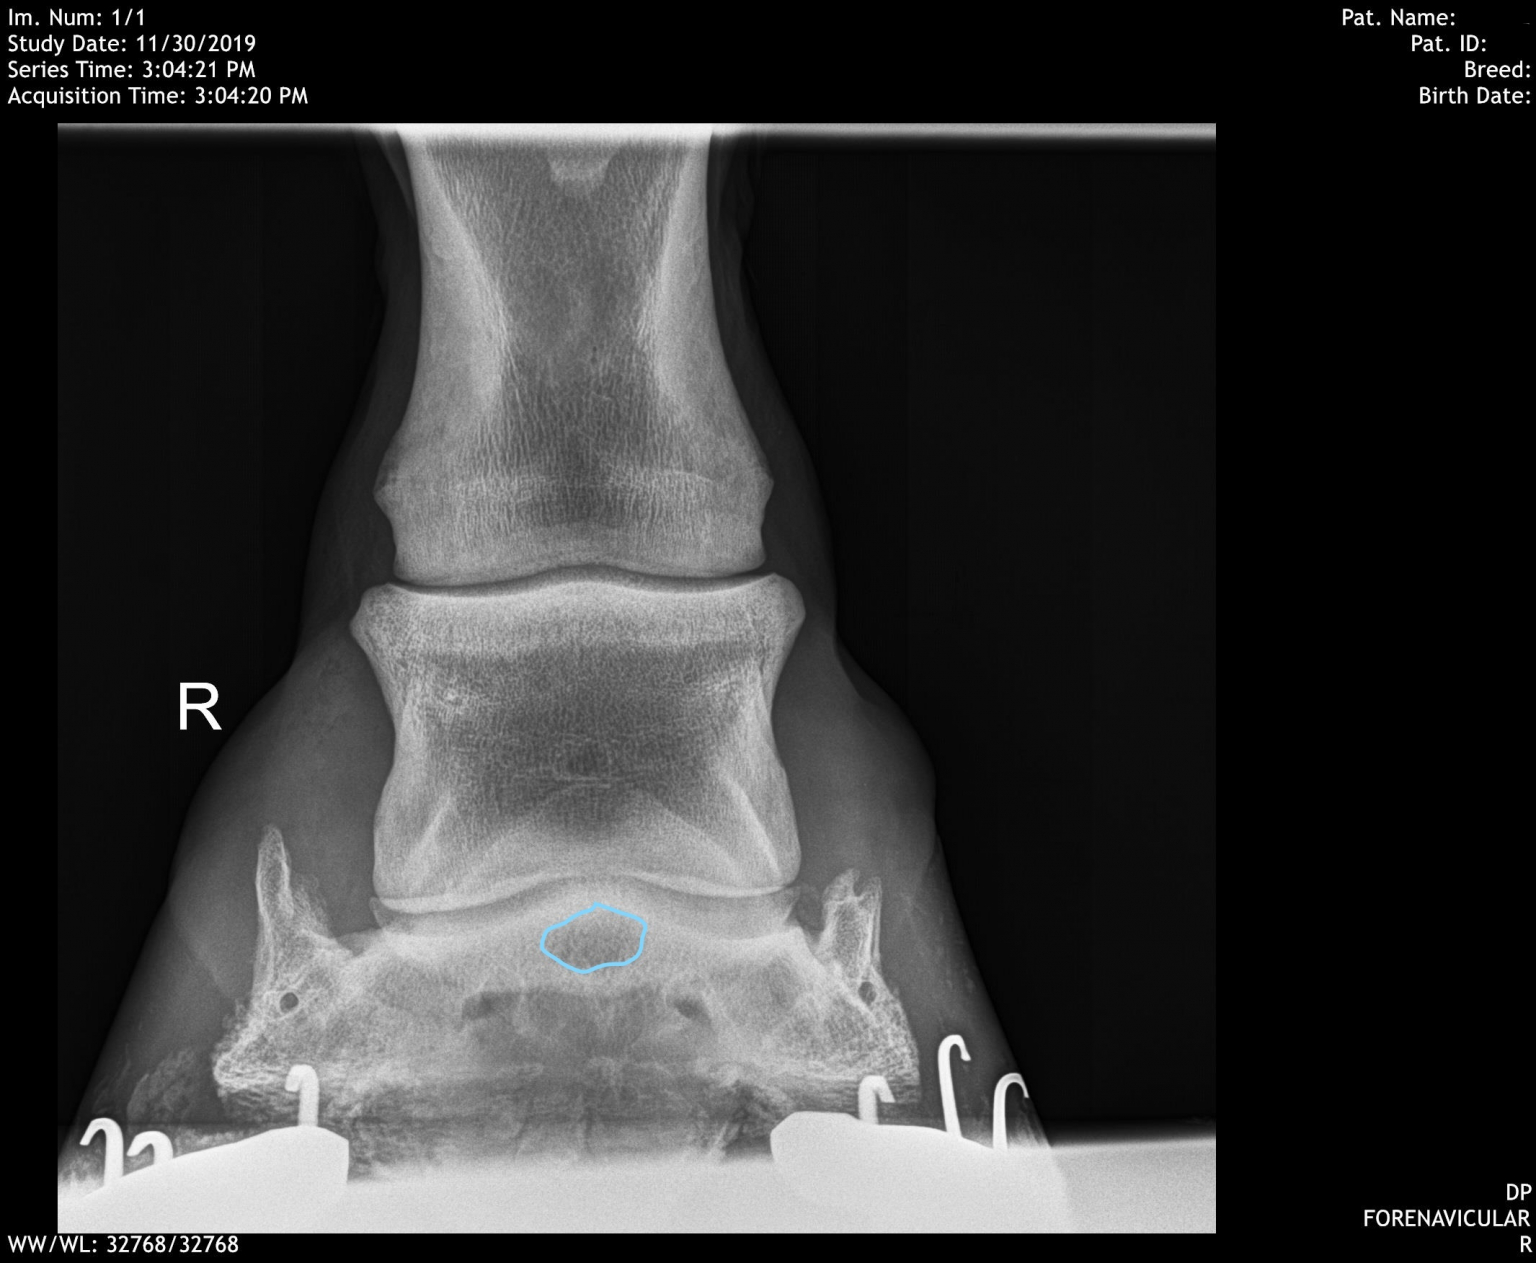

Equine Hock Spur. He believes the spurs could be. The distal intertarsal and tarsometatarsal joints are. The tarsus is a common etiology of hindlimb lameness in the horse. Web bone spavin is osteoarthritis, or the final phase of degenerative joint disease (djd), in the lower three hock joints. Web distal tarsitis, often referred to as “bone spavin”, is the most common cause of clinical lameness associated with the tarsus (or “hock”) in horses. Web our gelding's broken hock has healed with what the veterinarian calls bone spurs. Web distal hock joint pain may be a sequela of incomplete ossification of the central and third tarsal bones; Web lameness associated with the hock (tarsus) and proximal cannon (metatarsus) is not uncommon in both performance and leisure. It usually affects the two lowest joints of. Web disorders of the tarsus (hock) include the conditions known as bog spavin, bone spavin, and curb.

He believes the spurs could be. Web bone spavin is osteoarthritis, or the final phase of degenerative joint disease (djd), in the lower three hock joints. Web distal hock joint pain may be a sequela of incomplete ossification of the central and third tarsal bones; The tarsus is a common etiology of hindlimb lameness in the horse. Web our gelding's broken hock has healed with what the veterinarian calls bone spurs. It usually affects the two lowest joints of. Web disorders of the tarsus (hock) include the conditions known as bog spavin, bone spavin, and curb. The distal intertarsal and tarsometatarsal joints are. Web lameness associated with the hock (tarsus) and proximal cannon (metatarsus) is not uncommon in both performance and leisure. Web distal tarsitis, often referred to as “bone spavin”, is the most common cause of clinical lameness associated with the tarsus (or “hock”) in horses.